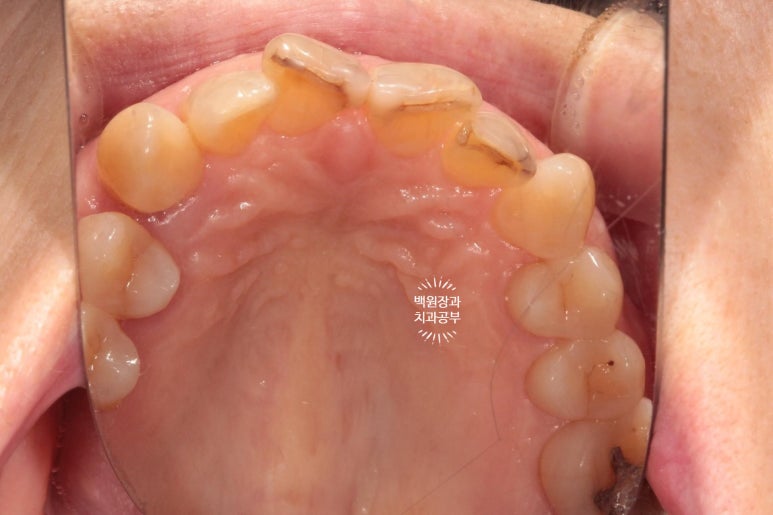

빼뚤빼뚤하기도 하면서, 금도 갖고 있었던 위 앞니들은 뒤에서 보면 이렇게 어둑하니.. 충치까지도 잘 보였습니다.

교합면에서 보았을 때 제작해드렸던 임플란트 크라운도 깔끔하게 잘 관리하고 계셨습니다.

3년이 지나니 상악동 뼈이식술을 했던 곳은 이제 거의 내 뼈와 하나가 된 것처럼 예쁘게 성숙된 모습을 보여주고 있고, 앞니 지르코니아 크라운은 꼼꼼히 관리해주신 덕분에 충치 하나 없이 신경치료 하지 않았음에도 아주 잘~ 쓰고 있는 모습을 확인할 수 있었습니다!